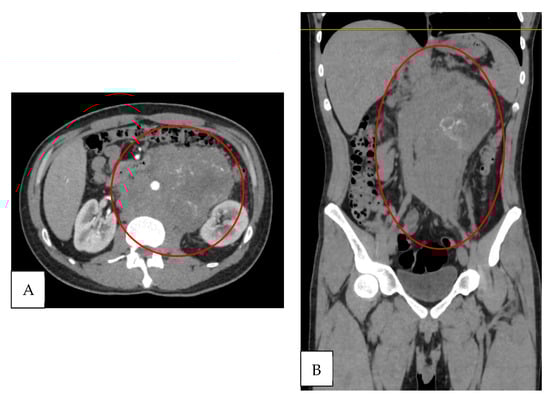

Contrast-enhanced computed tomography of the abdomen and pelvis revealed a conglomerated retroperitoneal mass measuring more than 5 cm, located in the paravertebral, retroclavicular, paraaortic, and intercavoaortic regions. The mass enhanced with contrast administration and caused displacement of adjacent vascular structures, including partial blockage of the abdominal aorta, superior mesenteric artery, and left renal artery (Figure 2A,B). The left testicle was heterogeneous with calcifications. The retroperitoneal mass was interpreted as a massive lymph node metastasis. Therefore, the cause of the clinical left varicocele was considered to be compression of the venous drainage.

Figure 2. Contrast-enhanced tomography. (A) Axial section: retroperitoneal conglomerate >5 cm with partial encasement of the abdominal aorta and superior mesenteric and left renal arteries (red circle). (B) Coronal section: retroperitoneal conglomerate with involvement of paravertebral, retrocrural, and paraaortic lymphadenopathy, with contrast enhancement (red circle).